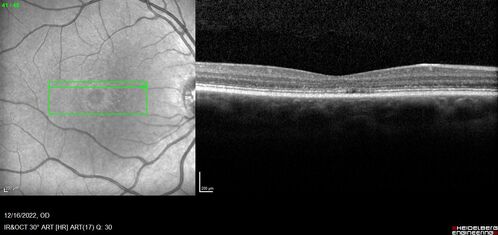

Stargardt Disease - Very Mild - 24 year old

This patient has 3 different ABCA4 mutations. His mother and sister have stargardts and his father has RP. His sisters images are also on Retinagallery.com